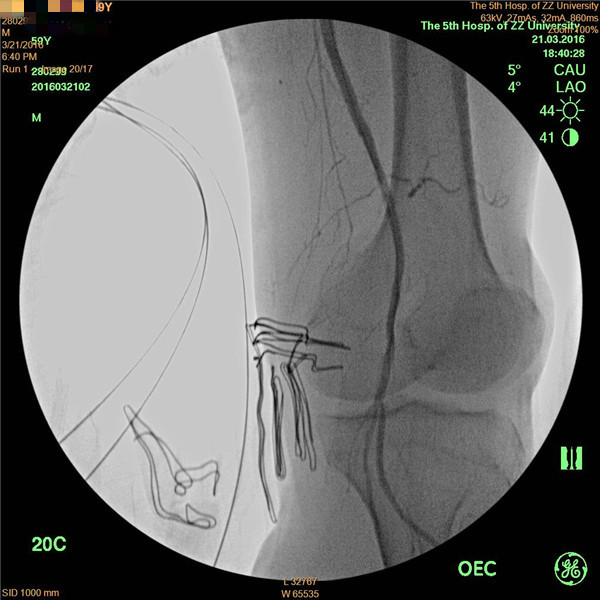

患者周先生,59岁,1年前无明显原因出现双侧小腿及足部发凉,活动后左足疼痛,3月前疼痛加重,出现左足第4及第5足趾发紫,并逐渐进展为足趾发黑、坏死,多处求医用药治疗,效果差,2周前左足疼痛进一步加重,并累及左足第3足趾发黑坏死,无法行走,严重影响了病人的生活质量(见图1)。慕名前来我院血管外科就诊。我院血管外科专家王兵教授为患者制定了详细的诊疗方案,下肢动脉CTA提示患者左侧股浅动脉多发粥样硬化斑块形成,管腔长段闭塞(见图2),明确诊断为“复杂下肢动脉硬化闭塞症”,积极术前准备后,王兵教授带领血管外科崔文军副主任、安乾主治医师、李攀峰医师给患者进行血管腔内介入治疗。术中DSA造影提示:股浅动脉长段闭塞,腘动脉通畅(见图3、图4)。单弯导管配合超滑导丝及微导丝,反复多次尝试顺行开通股浅动脉闭塞段均宣告失败,王兵教授决定采用逆穿技术,在DSA下穿刺腘动脉,成功后逆行置入单弯导管及超滑导丝,顺利开通股浅动脉闭塞段,逆行超滑导丝选入顺行单弯导管内,完成对接(见图5、图6),逆行导丝引出体外,引入球囊扩张股浅动脉闭塞段,股浅动脉闭塞段置入两枚金属裸支架后造影显示左下肢动脉全程通畅(图7、图8)。术后患者胫后动脉搏动恢复,静息性疼痛消失。 复查下肢动脉CTA:左下肢动脉血流通畅(图9)。

图5

图6